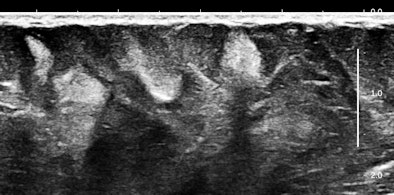

Of course, any of you might say that systemic mastocytosis is such a rare occurrence that one would probably never ever encounter one, but that is probably only true with fully and classically symptomatic cases. We have started looking at abdominal subcutaneous fat as part of our scanning routine, and guess what? This may not be such a rare occurrence at all. Here are some 15-MHz abdominal wall images of a 63-year-old hypothyroid woman who previously had a hysterectomy for a precancerous endometrial polyp:

Her history was interesting, with allergies that began in middle age and episodes of flushing during the past five years that she attributed to "hot flashes."

Soft, well-demarcated reflective nodules in subcutaneous fat are an Aunt Minnie of a sign. They are not palpable, and I suspect they can only be found by high-frequency ultrasound, which is perfect for outpatient screening applications. There may be a completely unexpected, relatively high prevalence of this finding, and it seems that multiple nodules may predispose several allergic disorders, including conditions such as irritable bowel syndrome (IBS), fibromyalgia, and possibly even exercise-induced asthma or postexertional hypotension and reactive tachycardia.